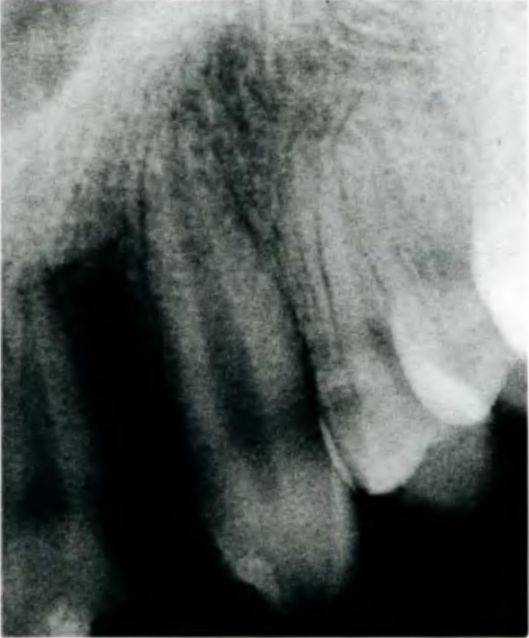

Рис. 5-ЗЬ. Рентгенограмма области отсутствующего верхнего бокового резца